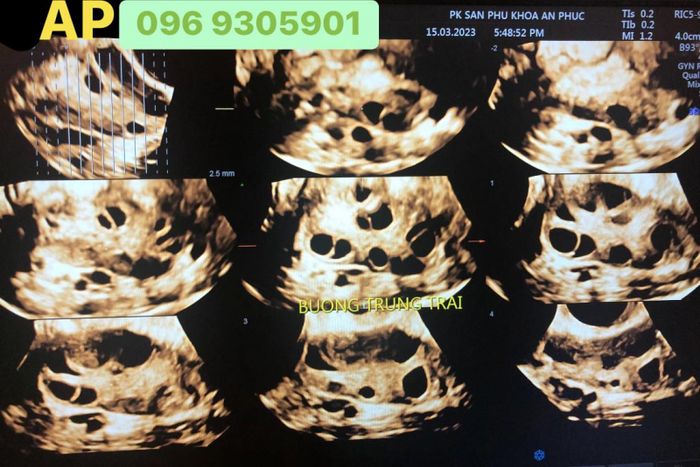

Khi tìm kiếm các phòng khám thai uy tín tại Hà Nội, Phòng khám sản phụ khoa - Hỗ trợ sinh sản An Phúc là một lựa chọn không thể bỏ qua. Đây là cơ sở khám chữa bệnh phụ sản nổi tiếng, thuộc hệ thống y tế lớn nhất cả nước. Phòng khám cung cấp dịch vụ khám thai định kỳ với chi phí hợp lý.

- Được trang bị thiết bị y tế hiện đại, giúp chẩn đoán và điều trị chính xác và an toàn.

Khi đến phòng khám, thai phụ sẽ được siêu âm và kiểm tra kỹ lưỡng để đánh giá sức khỏe và sự phát triển của thai nhi, cũng như phát hiện sớm các vấn đề sức khỏe. Phòng khám sản phụ khoa - Hỗ trợ sinh sản An Phúc còn tổ chức lớp học tiền sản miễn phí, cần đăng ký trước qua tổng đài hoặc trực tiếp tại phòng khám. Điều này giúp mẹ bầu yên tâm suốt quá trình thai nghén.